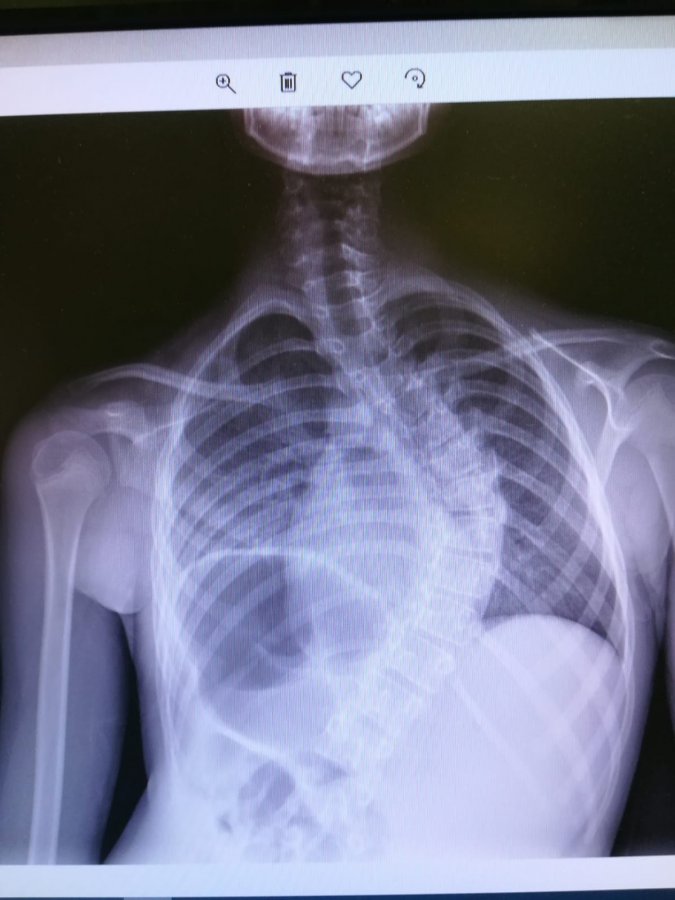

Operacja skoliozy kręgosłupa z prętami magnetycznymi jest niezwykle oszczędzająca dla dziecka. Wszystko dlatego, że kiedy dziecko rośnie, nie trzeba już wykonywać kolejnych operacji, aby wydłużać pręty. Zamiast tego, co trzy miesiące, przykłada się do pleców dziecka specjalne urządzenie, które rozciąga pręty. Bezboleśnie. Wszystko trwa kilkanaście sekund. Zwykle jest już po wszystkim, zanim w telefonie włączy się bajka, która ma uspokoić dziecko.

Pierwsza tego typu operacja odbyła się w jesienią zeszłego roku. Przygotowania do niej trwały kilka miesięcy. Całość koordynował dr Paweł Grabala. On też stoi za tym, że klinika stała się jednym z 24 ośrodków szkoleniowych na świecie w chirurgii kręgosłupa prestiżowej branżowej organizacji Scoliosis Research Society.

W kraju ostatnio zasłynęliście z operacji kręgosłupa z prętami wydłużanymi magnetycznie. Opowie Pan, jak to wszystko wygląda od strony lekarza?

- To był nasz początek. Długo się do tego przygotowywaliśmy razem z dr Pawłem Grabalą. Do wykonania pierwszego zabiegu w Białymstoku zaprosiliśmy dr Noelle Larson z Mayo Clinic z USA. To światowej klasy specjalistka, która chętnie dzieli się swoją wiedzą. Zabieg jest bardzo medialny, ale z technicznego punktu widzenia, nie jest szczególnie skomplikowany.

Później na kręgosłupie zrobiliśmy już kilka dużo trudniejszych zabiegów, ale już się nimi nie chwaliliśmy. Na przykład, na początku stycznia odwiedził nas prof. Ilkka Juhani Helenius, który jest kierownikiem Oddziału Chirurgii Kręgosłupa w Klinice Ortopedii Dziecięcej w Uniwersyteckim Szpitalu w Turku (Finlandia). Wykonał on dwa skomplikowane zabiegi korekcji skolioz kostnopochodnych w przebiegu rzadkich wad wrodzonych kręgosłupa u 7 i 8 letnich dzieci. To bardzo rzadkie operacje. Nasi pacjenci szukali pomocy po całym świecie, ale koszty operacji w wysokości kilkuset tysięcy dolarów przerastały możliwości ich bliskich. Dlatego łatwiej było nam zaprosić do nas operatora i te zabiegi zrobić u nas. Trzeba jednak wziąć pod uwagę, że to były zabiegi o ogromnym ryzyku. Polegały one na częściowej resekcji kręgów, a pacjent operowany był z dwóch dostępów. Na co dzień nie ma wielu takich przypadków. W zasadzie w całej Skandynawii takie zabiegi wykonuje tylko prof. Helenius i to jest wystarczające.

- Zaprosiliśmy do siebie doktora Darryla Antonacci z Nowego Jorku z Uniwersytetu Princeton. Jest on jednym z twórców metody ASC (ang. Anterior Scoliosis Correction), która moim zdaniem, jest rewolucją w leczeniu skolioz. Do tej pory leczenie polegało na odprostowaniu kręgosłupa i zaimplantowaniu sztywnych prętów. One ten kręgosłup usztywniały do końca życia. Owszem, w stosunku do tego co było przed operacją, komfort życia się poprawiał. Jednak aktywność fizyczna takiego pacjenta nie jest tą, o jakiej marzymy jako lekarze. Nie ma mowy o tańcu, balecie, czy zawodowym uprawianiu sportu. Dlatego też ortopedzi stosowali takie zabiegi tylko w dużych deformacjach. Punktem wyjścia dla techniki ASC była metoda VBT (ang. Vertebral Body Tethering), która może być zastosowana tylko dla pacjentów nadal rosnących. Natomiast technika ASC autorstwa dr Antonacci, dr Betz i dr Cuddihy polega na tym, że można ją zastosować nawet u pacjenta z zakończonym wzrostem kostnym. Technika ASC polega na wstępnym uelastycznieniu deformacji, implantacji specjalnych śrub do trzonów kręgów i ostatecznie korekcji skrzywienia poprzez połączenie implantów elastyczną taśmą. Technikę tę można stosować zarówno u pacjentów w trakcie wzrostu, jak również po jego zakończeniu. W przypadku pacjenta nadal rosnącego wstępna korekcja jest częściowa, kolejna dokonuje się w trakcie wzrastania poprzez blokowanie chrząstek wzrostowych trzonów po stronie wypukłej skrzywienia. Trudnością jest właściwe zaplanowanie, jak również sama technika zabiegu, która jest bardzo wymagająca. Taki zabieg doktor Antonacci wykonał dla jednej z tancerek, finalistek w angielskiej wersji „Mam Talent”. Na zabieg do Nowego Jorku wysłał ją jeden z jurorów. A dziewczyna nadal tańczy w swoje grupie i spełnia swoje marzenia.

- Nie. To mogą być krzywizny rzędu 70, a nawet 90 stopni. Oczywiście pacjent musi przejść kwalifikację do zabiegu. Co ciekawe, metodę VBT i ASC w ortopedii wykorzystujemy od bardzo dawna. Korygujemy nią zaburzenia osi kończyn górnych i dolnych u dzieci blokując czasowo chrząstki wzrostowe. Nigdy jednak tego nie robiliśmy w kręgosłupie. Ten zabieg wykonamy jako pierwsi w kraju. W Europie tylko cztery ośrodki tak operują. W USA też tych zabiegów nie jest dużo.